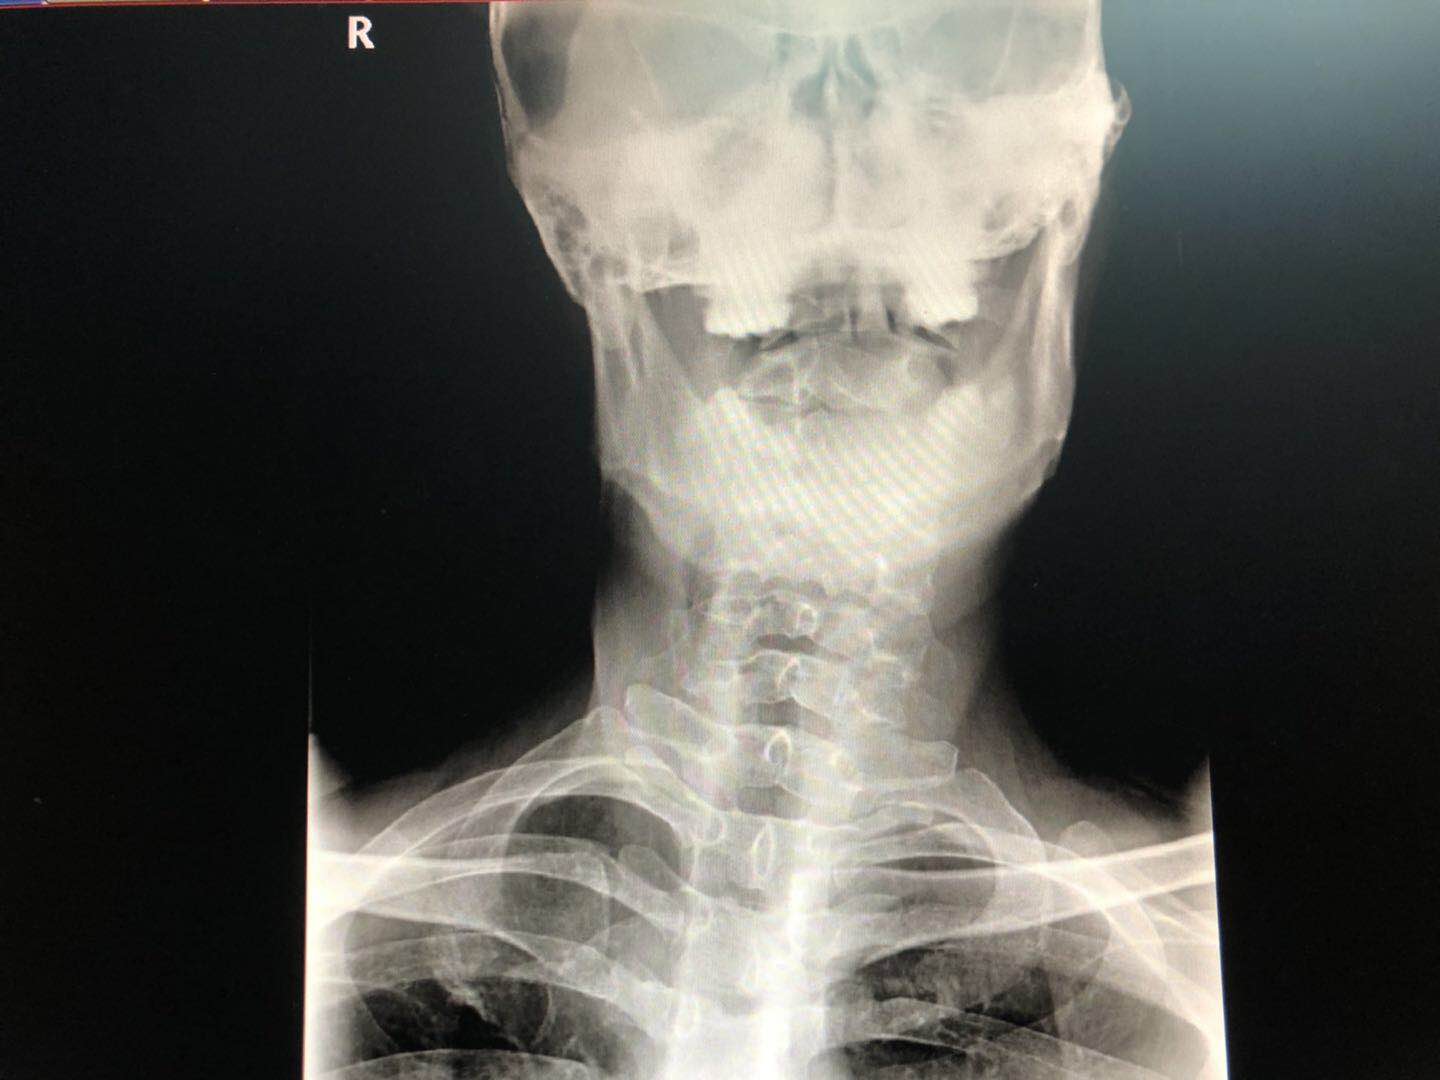

医生考虑诊断是:右侧的肌性斜颈,打算给罗先生做手术!

3、术后一般不用拍X光片复查,因为基本看不出什么来!术前拍的X光片,这是手术前常规,病历里必须要有的,需要引起注意;